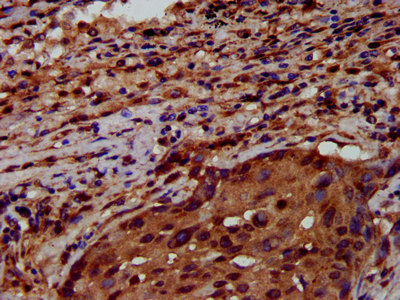

• IHC image of CSB-PA019892LA01HU diluted at 1:600 and staining in paraffin-embedded human lung cancer performed on a Leica BondTM system. After dewaxing and hydration, antigen retrieval was mediated by high pressure in a citrate buffer (pH 6.0). Section was blocked with 10% normal goat serum 30min at RT. Then primary antibody (1% BSA) was incubated at 4°C overnight. The primary is detected by a biotinylated secondary antibody and visualized using an HRP conjugated SP system.

IHC 1:500-1:1000